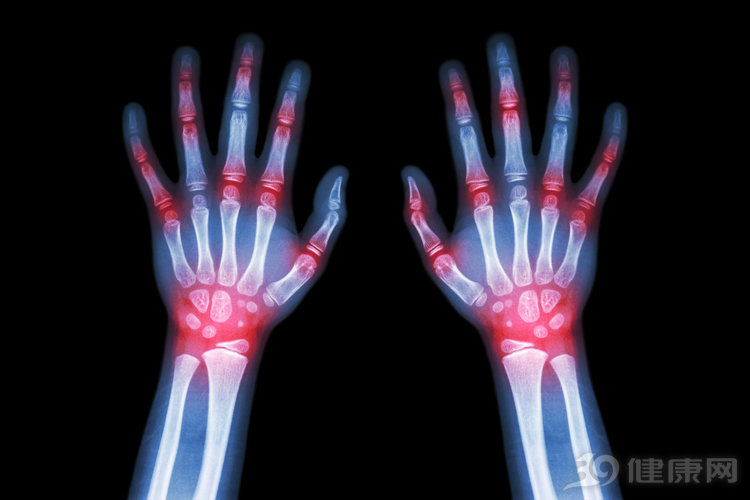

1.当痛风轻微,不常见且不复杂时,可以通过改变饮食和改变生活方式来治疗。当痛风发作频繁时,常常会发生尿酸肾结石,存在痛风石,药物通常用于降低尿酸血液水平。除了秋水仙素,其他的治疗方法也是比较有效的。

3.第二类药物是在急性痛风发作期间用于减轻疼痛和炎症的药物。秋水仙碱(Colcrys)和NSAID都可以在急性痛风发作期间使用,以减少炎症和疼痛。